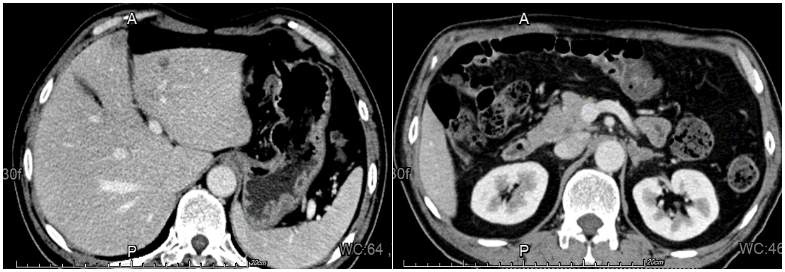

全腹部增强CT(2022-05-30):1、左侧肾上腺结节,较大者直径约1.3cm,增强呈不均匀强化,结合病史,不除外转移瘤可能。2、肝脏左叶低密度影,增强边缘可疑强化,转移?

图2.全腹增强CT

二线治疗第1周期后复查增强CT(2022-07-25):与2022-06-29CT对比:1.左肺上下叶肿瘤性病变(较大截面大小约5.9cm×4.5cm)伴阻塞性炎症,病灶较前缩小;肿块旁多发小结节,考虑转移灶,较前缩小;左肺门及纵隔多发转移瘤,较前缩小。2.右肺上叶及双肺下叶点状影,左肺下叶点状钙化灶。与2022-05-30CT对比:1.左侧肾上腺结节(较大者直径约1.0cm)考虑转移,病灶较前缩小。2.原片所示肝内转移灶本次检查显示欠清晰。

二线治疗第3周期后复查增强CT(2022-09-25):与2022-07-25CT对比:左肺上下叶肿瘤性病变伴阻塞性炎症(较大截面大小约5.1cm×3.2cm),肿块较前大致相仿,周围炎症较前略有吸收、减少;左肺门及纵隔多发淋巴结转移,部分较前略显缩小。与2022-07-25CT对比:1.左侧肾上腺肿块(最大横截面约3.4×2.1cm),较前增大,考虑肾上腺转移。2.肝右叶小囊肿可能。

二线治疗第3周期后疗效评估结果:肺部及纵隔淋巴结病灶为PR;肝脏病灶为CR;左肾上腺病灶为PD;总体疗效评价为PR。